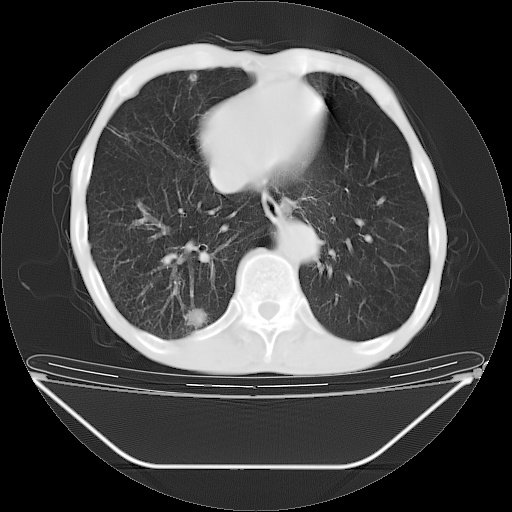

以下是引用lijuanln在2008-8-25 21:52:00的发言:[br]考虑右肺肿瘤并肺内转移,左肺上叶结核钙化;腰椎转移。